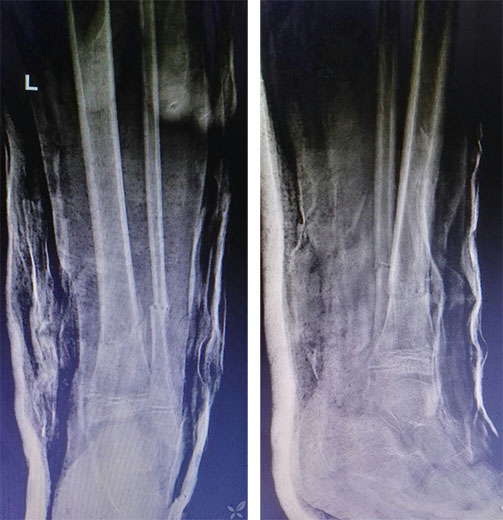

复位后20天复查X线,基本满意,可见连续骨痂通过骨折端,为避免长期跖屈导致跟腱及屈趾肌腱挛缩粘连,改踝关节功能位固定